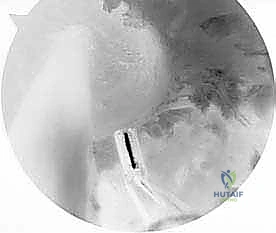

- الجراحة المجهرية وتنظير المفاصل بدقة 4K: يستخدم الدكتور هطيف أحدث تقنيات مناظير الركبة (Arthroscopy) المزودة بكاميرات عالية الدقة 4K، مما يتيح له رؤية أدق التفاصيل داخل المفصل، وتشخيص الأضرار المجهرية، وإجراء الجراحة بأقل تدخل جراحي ممكن (Minimally Invasive).

* التصوير بالرنين المغناطيسي (MRI): يوفر صورة مفصلة للأنسجة الرخوة. يحدد حالة الطعم المزروع سابقاً (هل هو ممزق، متآكل، أم سليم ولكنه غير فعال؟)، ويقيم حالة الغضاريف الهلالية والمفصلية.